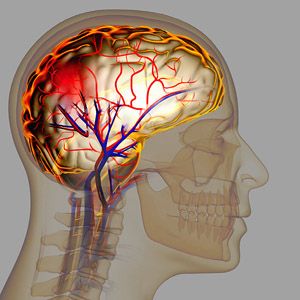

뇌졸중은 신속한 대응이 중요한 질환입니다. 전조증상을 빠르게 인식하고 즉각적인 조치를 취하는 것이 생명을 구하고 후유증을 최소화하는 데 중요한 역할을 합니다.

뇌졸중 전조증상을 인식하고 신속하게 대응하는 것은 매우 중요합니다. 체크리스트를 통해 전조증상을 빠르게 확인하고, 필요한 경우 즉각적인 응급 처치를 시행하세요. 또한, 건강한 생활 습관을 유지하여 뇌졸중을 예방하는 것이 중요합니다.